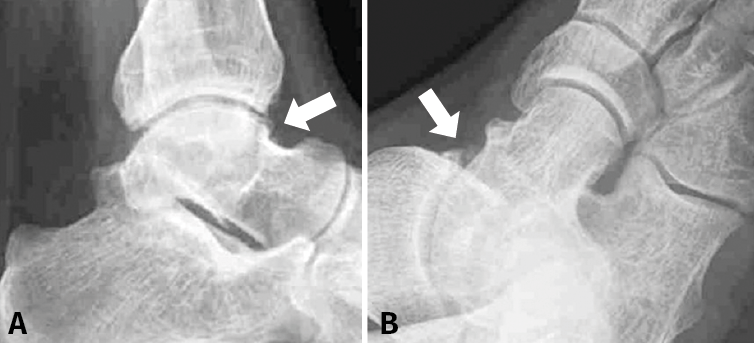

En cuanto a las pruebas de imagen, se solicitan las proyecciones radiográficas estándar, anteroposterior y lateral, y oblicua que suelen ser suficientes para demostrar la presencia de osteofitos (Figuras 2A y 2B)(20). Sin embargo, se suele solicitar también un estudio de resonancia magnética (RM), útil para descartar otros diagnósticos como lesiones osteocondrales, cuerpos libres y/o fracturas por estrés, que son de diagnóstico radiográfico tardío(11,21), además de poder detectar la patología de las partes blandas(22). Por último, es útil dado que algunos osteofitos tibiales o astragalinos de localización anteromedial podrían no ser detectados radiográficamente debido a la superposición de imagen que se produce entre la parte lateral del cuello y el cuerpo del astrágalo(11). Y, aunque los primeros estudios informaron una relativamente baja sensibilidad de la RM para el diagnóstico en el tobillo(23,24,25,26), la literatura reciente demuestra ya lo contrario(27). Este bajo rango inicial estaría probablemente más bien relacionado con el nivel de experiencia en la interpretación de la RM de tobillo que con la propia sensibilidad de la prueba.

Figura 2. Estudios de imagen: las radiografías lateral (A) y oblicuas (B) se utilizan para detectar la presencia de osteofitos.